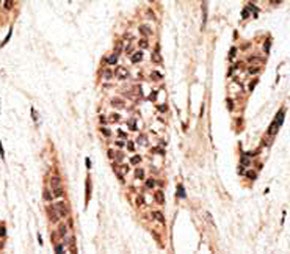

IHC analysis of FFPE human breast carcinoma tissue stained with the TAP1 antibody